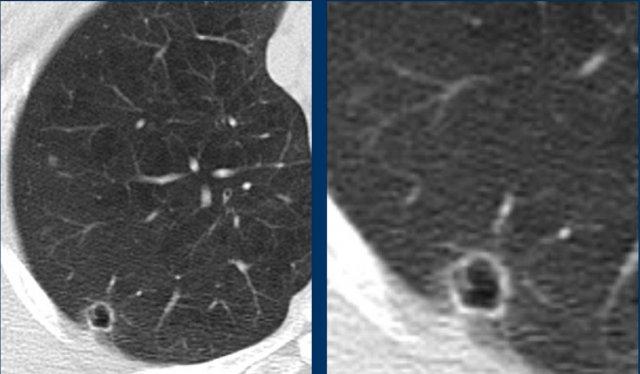

Các hình ảnh này của một nữ bệnh nhân 60 tuổi mắc bệnh Sjögren, được chỉ định chụp HRCT để tầm soát bệnh phổi kẽ.

Nhận xét

Có một vài nang (nhiều hơn bốn nang, không hiển thị hết), do đó nhiều khả năng đây là bệnh phổi dạng nang. Có một vùng kính mờ ở các trường phổi dưới và một số vách gian tiểu thùy dày.

Bàn luận

Sự kết hợp giữa các nang và kính mờ giúp thu hẹp chẩn đoán phân biệt còn LIP và DIP.

Ở bệnh nhân mắc bệnh Sjögren, chẩn đoán là LIP.